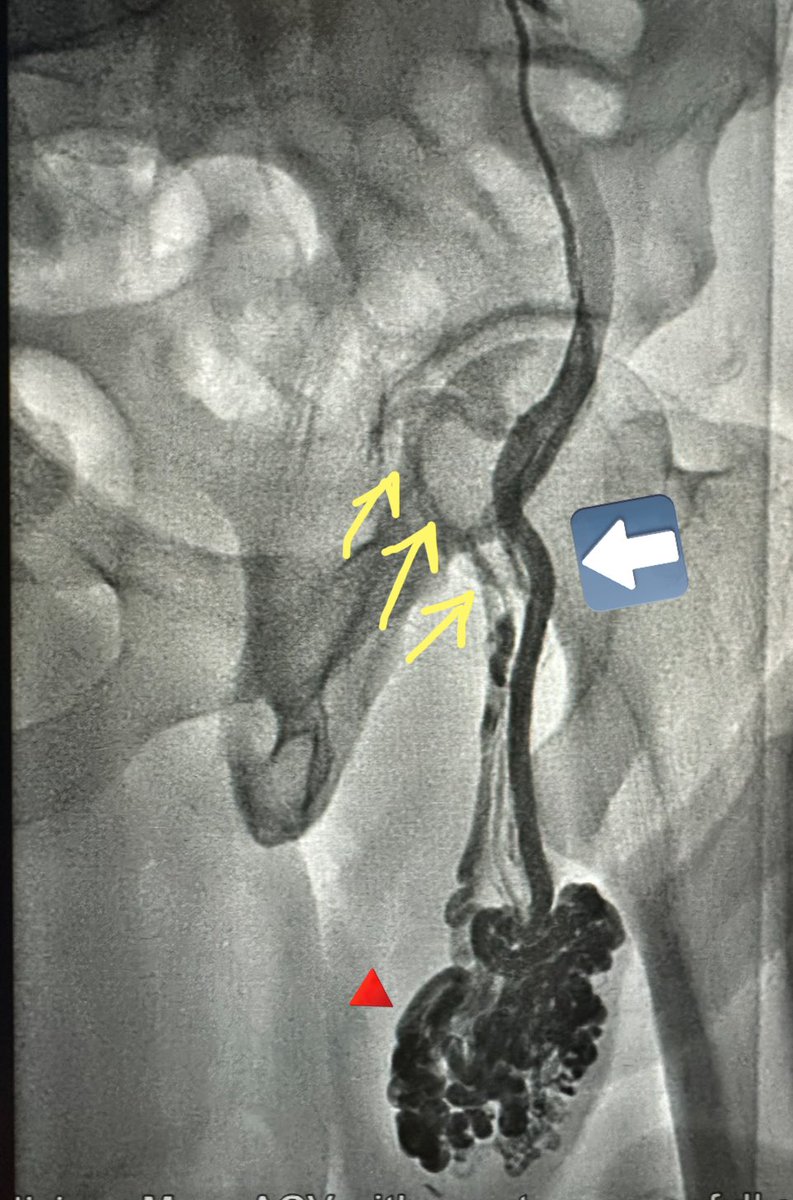

١٥- هذه الطريقة فشلت بسبب أن الربط يتم بمكان واحد ومن المعلوم ان الوريد الخصوي يغذيه اوردة كثيرة جداً وربطه في مكان واحد غير فعّال ابداً. أوردة كثيرة تتصل بالوريد الخصوي ، منها اوردة جوانب الظهر ، غلاف الكلية ، ووريد القولون (السهم الملون) كما بالصورة المرسوم وبصورة واقعية من اجراء القسطرة والعلاج بالصمغ الطبي. لا تجد احداً من جراحين المسالك يتكلم عن هذه التفاصيل حتى بالدراسات بسبب انها لا تتوضح جراحياً اساساً.

١٧- ماذا عن تجمع الحرارة والدم حول الخصية؟ هذه الدوالي تمتد الى حول الخصية والبربخ. الربط الجراحي يكون بمستوى واحد فقط فوق الخصية مع ترك كل هذه الاوردة المتضخمة المحتقنة بالدم حول الخصية. لذلك في غالبية الحالات يكون التحسن بالاعراض والحيوانات المنوية مؤقتاً. هذه حالة لدوالي تم ربطها جراحياً ، لاحظ انه بالاضافة الى عدم ربط كل الاوردة عند مكان الشق الجراحي(وريد داخلي كبير لم يربط بالأزرق ، أوردة خارجية خلفية لم تربط بالأصفر، شبكة دوالي كبيرة -سهم احمر- محتقنة حول الخصية لم يتم لمسها).